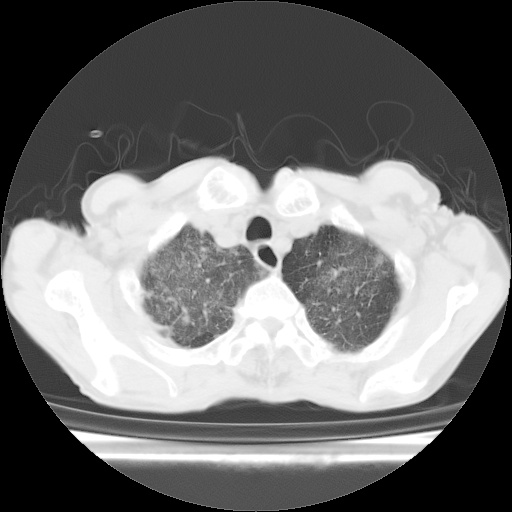

病人发热、气促就诊。原二周前已行ct扫描,当时诊断为双肺下叶、右肺中叶支气管扩张并感染,双肺上叶片状渗出性病变。今天复查胸部ct,双肺下叶支气管扩张并感染病灶较前明显吸收,但双肺上叶渗出性病变较范围较前明显增大。

双肺多发大片状、斑片状高密度渗出影,部分实变,考虑病毒性肺炎。